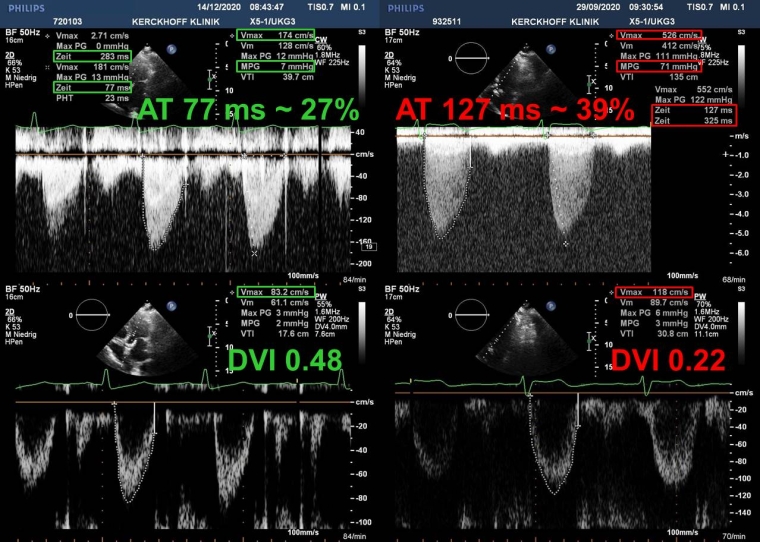

For aortic PVs, a peak velocity >3 m/s should alert the clinician and lead to prompt determination of the DVI and acceleration time (AT). Obstruction becomes likely if the DVI is <0.25 along with a more rounded parabolic (instead of triangular) and late peaking transvalvular continuous-wave Doppler spectrum with an AT >100 ms or >0.37 when indexed to the LV ejection time because the AT is highly dependent on heart rate. These two parameters are also less flow-dependent than transvalvular velocities and also applicable in case of concomitant prosthetic aortic regurgitation (AR) (Figure 1). Typical Doppler findings of an obstructed BPV are displayed in Figure 2.

Figure 2. Continuous (top) and pulsed-wave Doppler recordings (bottom) of a normal (left) and degenerated bioprosthetic valve in the aortic position (right).

With prosthetic obstruction, the mean gradient is increased to 71 mmHg (>20) and the Doppler velocity index (DVI) decreased to 0.22 (<0.25). In addition, the acceleration time (AT) from onset of aortic flow to peak velocity is increased to 127 ms (>100), corresponding to 39% (>37) of the ejection time.